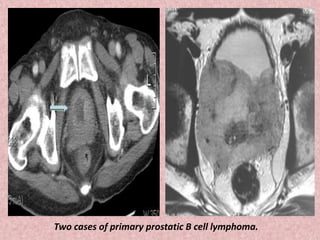

Two cases of primary prostatic B cell lymphoma.

Two cases ofprimary prostatic B cell lymphoma.